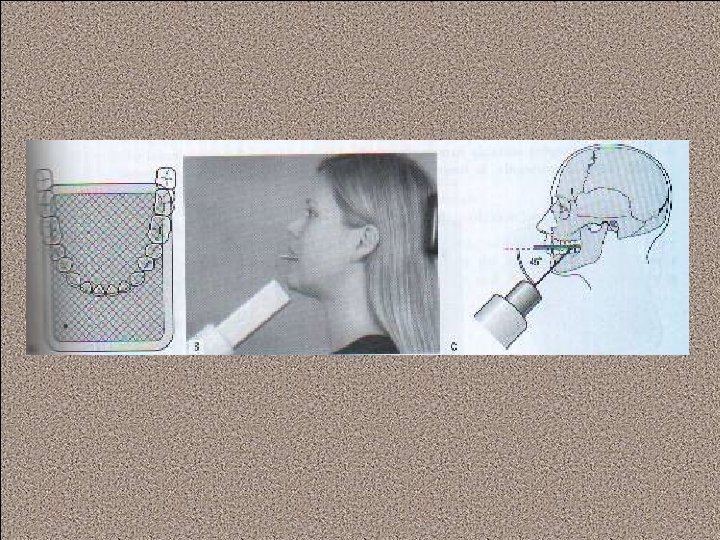

Technique requirements when using a tab attached to the image receptor The appropriate sizes film packet or phosphor plate is selected and the tab attached, orientated appropriately for horizontal or vertical projections: Large film (31*41) or long film (53*26) is used for adult, and small film (22*35) for children under 12 years.

The patient is positioned with the head supported and with the occlusal plane horizontal. The shape of the dental arch and the number of film required are assessed. The operator holds the tab between thumb and forefinger and insets the image receptor into the lingual sulcus opposite the posterior teeth.

The anterior edge of the image receptor should be positioned opposite the distal aspect of the lower canine

The tab is placed on to close the teeth firmly together on the tab. The patient closed the teeth firmly together on the tab. The operator assesses the horizontal and vertical angulations and positions the X-ray tubehead so that the X-ray beam is directly through the contact areas, at rught angles to the teeth and image receptor, with an approximately 5 o-8 o downward vertical angulation